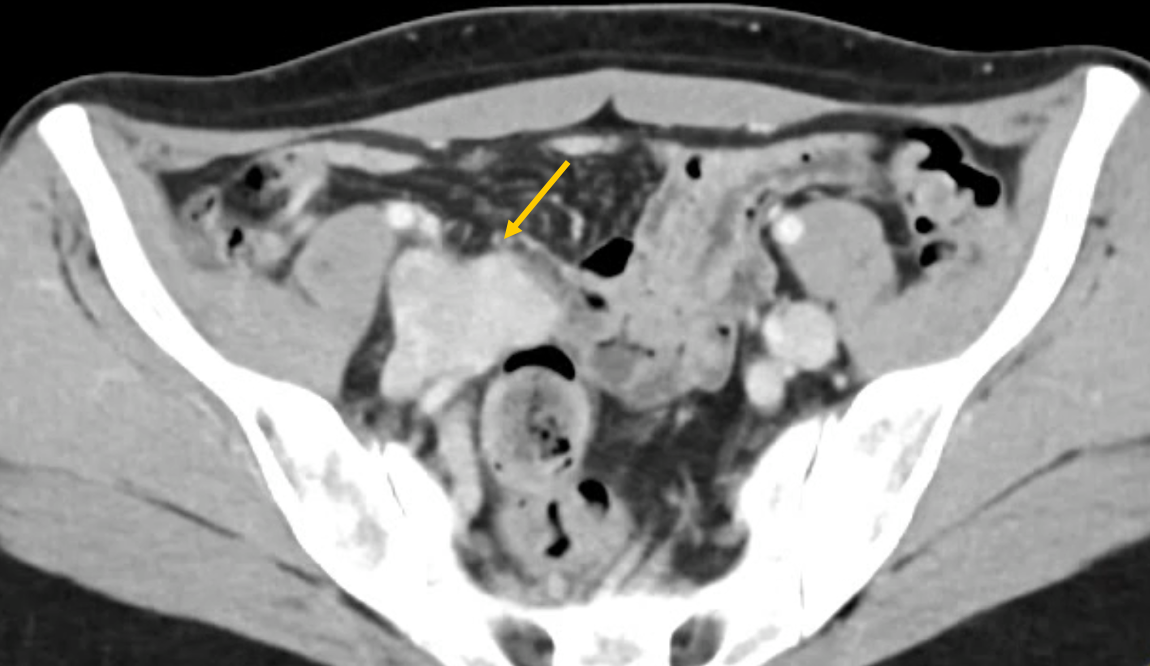

A lower extremity venous duplex ultrasound is performed and is negative. A computed tomographic venogram is obtained and demonstrates a lobulated lesion in the right iliac fossa; the differential diagnosis given was venous aneurysm, vascular malformation, and possibly a mass (Figure 1, yellow arrow). Her primary care physician initiates enoxaparin and sends her to us for consultation.